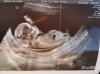

Super gratuluje! Akurat tez bym powiedziala ze dziewczynkaNo i prawdopodobnie dziewczynka. Wady wykluczone. Jak to stwierdził lekarz obraz i pomiary książkowe

Gratulacje!No i prawdopodobnie dziewczynka. Wady wykluczone. Jak to stwierdził lekarz obraz i pomiary książkowe![]()